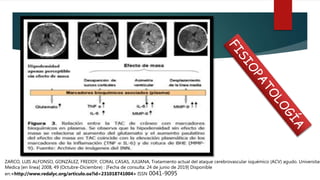

FISIOPATOLOGÍA

ZARCO, LUIS ALFONSO, GONZÁLEZ, FREDDY, CORAL CASAS, JULIANA, Tratamiento actual del ataque cerebrovascular isquémico (ACV) agudo. Universitas

Medica [en linea] 2008, 49 (Octubre-Diciembre) : [Fecha de consulta: 24 de junio de 2019] Disponible

en:<http://www.redalyc.org/articulo.oa?id=231018741004> ISSN 0041-9095